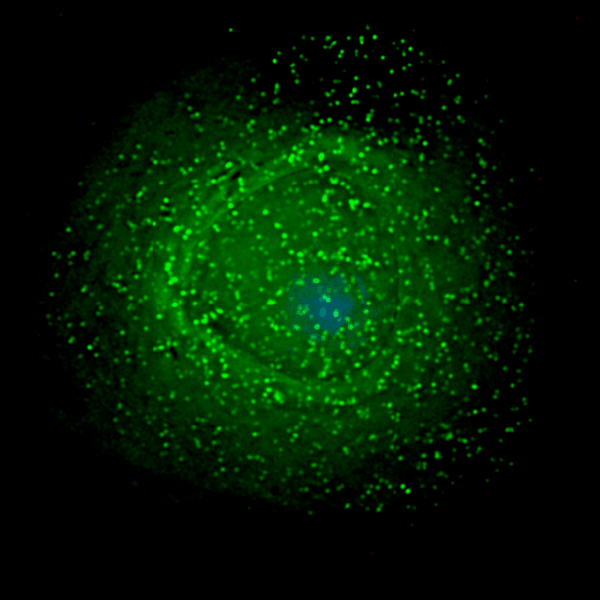

Virus s’assemblant à la surface d’un macrohage Photo: Gross L, PLoS Biology Vol.